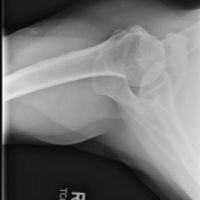

according to Letournel and Judet [2], detaching the acetabular roof and the adjoining part of the iliac wing while respecting the continuity of the pelvic ring (Fig. 2).

Figure 2: Post-operative computed tomography scan of fracture (a) Sagittal view (b) Coronal view.